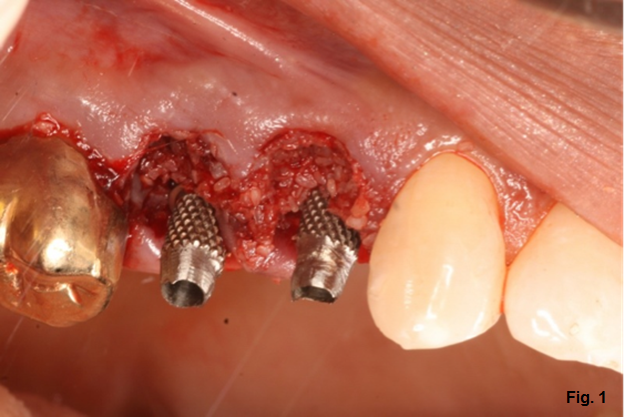

The first step is to start with an implant temporary abutment. These are typically long, narrow cylinders made of plastic or metal (Fig. 1) that you add material to achieve your desired form. Both the plastic and metal versions have their positives and negatives; I generally prefer the metal versions when available because they’re thinner and give me more room to work. The big downside to the metal versions is the fact that their color can bleed into your provisional.